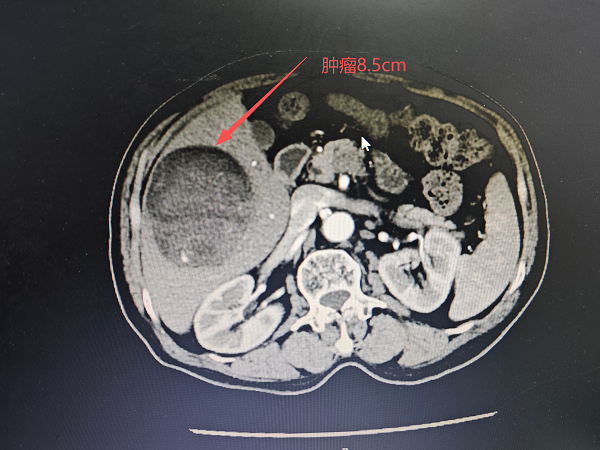

3. 经导管肝动脉化疗栓塞术(TACE):患者是一名73岁的男性,检查发现肝占位性病变50天,腹部CT可见右肝1个大小约8.5cm病灶,肝左叶及右叶均可见一0.5cm大小病灶,考虑肝恶性肿瘤伴肝内转移,于2026年2月14日在宜春市人民医院行经导管肝动脉化疗栓塞术。于2026年3月15日在我院由郭陵副主任医师、江福生主任医师(宜春市人民医院) 龙旺主治医师在局麻下行经导管肝动脉化疗栓塞术,手术顺利,患者术后无明显并发症。较大的肝恶性肿瘤无手术切除指征,可行经导管经导管肝动脉化疗栓塞术通过缩小肿瘤,寻求手术机会,或者延长患者生命,改善患者生活质量。